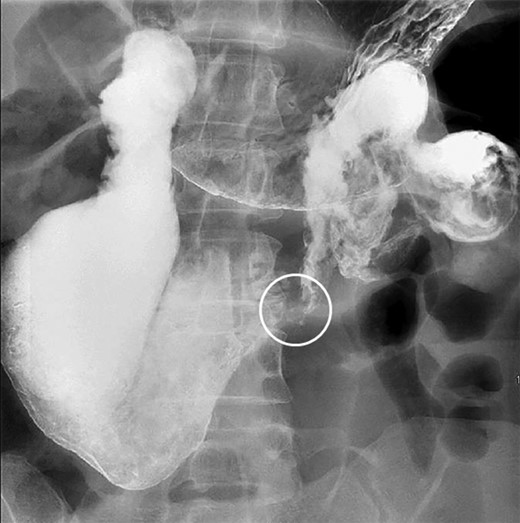

Immediately prior to presentation, the patient experienced another episode of nausea, abdominal pain, distention, and diarrhea. Again, the patient denied any weight loss and did not exhibit signs or symptoms of systemic infection. Computed tomography (CT) of the abdomen and pelvis with oral and intravenous contrast as well as an upper GI series demonstrated a significantly dilated duodenum with a sharp transition to collapsed small bowel (Fig. 1). CT also demonstrated an acutely angulated SMA with compression of the duodenum between the SMA and the aorta (Fig. 2). Endoscopic evaluation did not demonstrate any evidence of mechanical obstruction of the duodenum.

Upper GI demonstrating duodenal dilation with decompressed small bowel distal to a sharp transition point (circle).